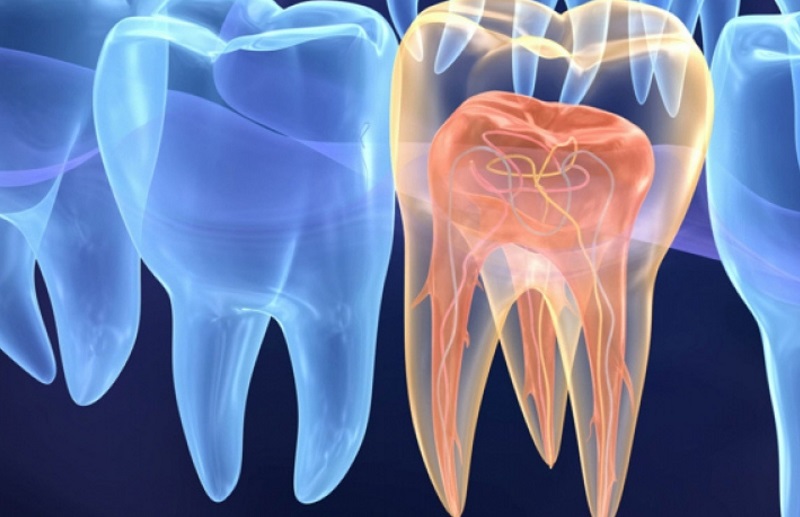

Endodontia

Desvitalizações e tratamentos dos canais nervosos e tecidos que rodeiam a raiz do dente.